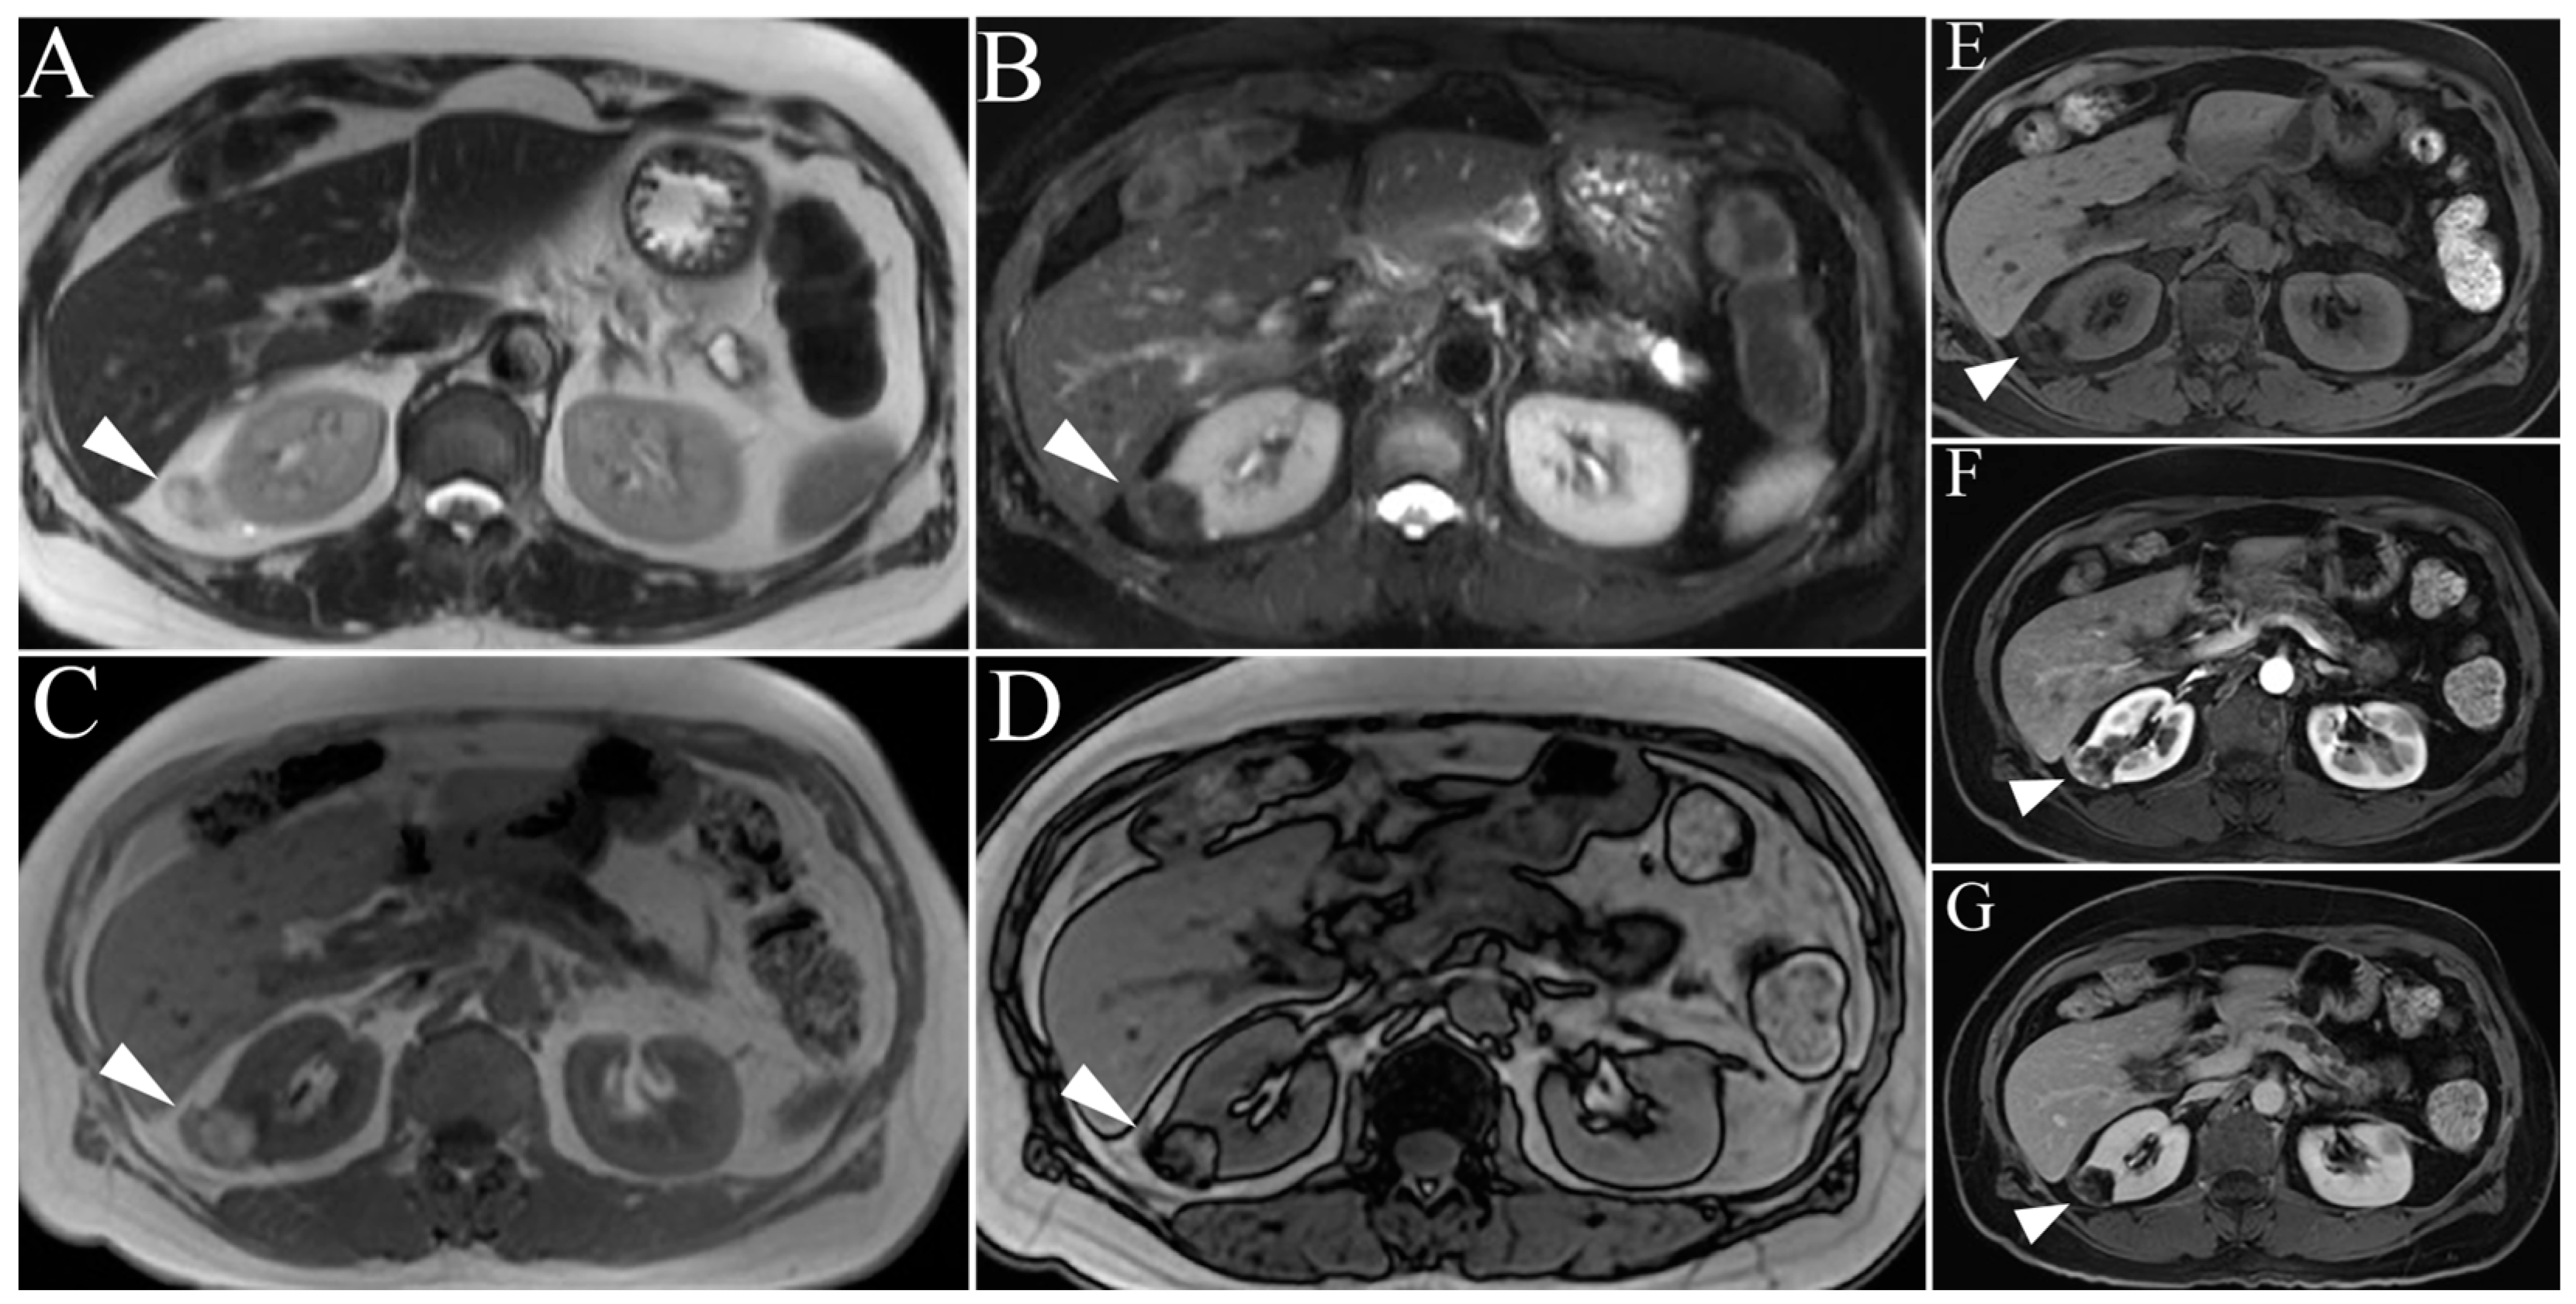

4.1. Angiomyolipoma

4.2. Oncocytoma

5. Malignant Renal Tumors

5.1. Clear Cell Renal Cell Carcinoma

| Angiomyolipoma | High T2-intensity signal due to fat content. Low T2 on fat-suppressed images. Microscopic, intracytoplasmic fat made apparent with in- and out-of-phase GRE |

| Lipid-poor Angiomyolipoma | T2-hypointense Macroscopic fat and/or absence of fat High arterial enhancement with subsequent washout |

| Oncocytoma | T2-iso-to-hyperintense relative to normal parenchyma Central/eccentric T2-hyperintense scar Delayed enhancement of a central scar Segmental enhancement inversion pattern |